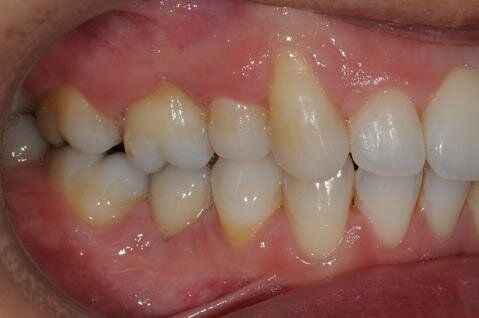

All’esame clinico del viso si osservava una sostanziale simmetria bilaterale e corrette proporzioni facciali verticali frontali e laterali (Figg. 1a-1c). Il sorriso presentava un’adeguata esposizione degli incisivi superiori e dei corridoi buccali e la centratura della linea mediana superiore rispetto al volto. All’ispezione del cavo orale, invece, si riscontrava una lieve deviazione della linea mediana inferiore verso destra di circa 1 mm, con contestuale II Classe canina a destra (Figg. 2a-2c). La mancanza del primo molare inferiore di destra aveva prodotto lo spostamento mesiale, la mesio-inclinazione del secondo e terzo molare inferiore e l’estrusione del primo molare superiore. A sinistra, invece, era riscontrabile una I Classe canina e molare. Erano presenti un moderato affollamento nell’arcata superiore ed un lieve disallineamento degli incisivi inferiori. L’overjet era lievemente aumentato e l’arcata superiore appariva lievemente contratta, soprattutto a destra. Erano presenti recessioni gengivali multiple.

Figg. 2a-2c - Foto intraorali pretrattamento: visioni frontale (a), laterali (b).